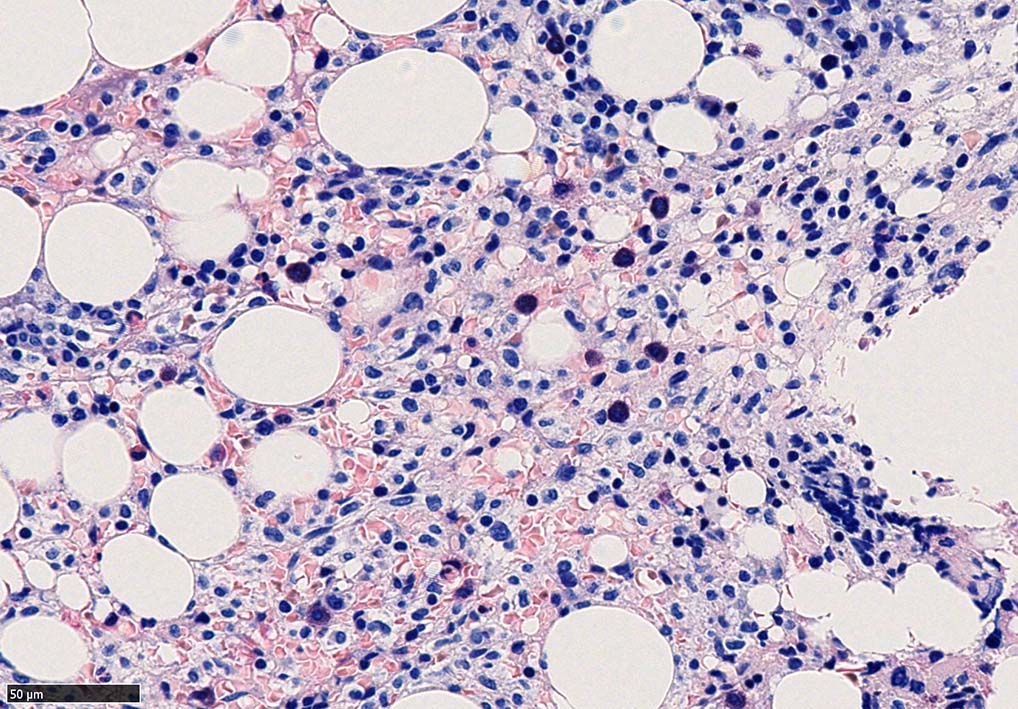

ASD-Giemsa陰性の細胞がシート状に増殖する. 核はクロマチン濃染, 核小体は不明瞭.類円形, 卵円形, くびれを持つ多稜形核, 長円形いびつで屈曲した核, など多彩. 細胞質は淡清色調, 広く淡明. 赤芽球血島は幼若赤芽球のみで形成される異形成像を示す. やや離れて成熟赤芽球が疎な集簇を示す.

骨髄生検組織を使ったFCMのため, 細胞数が少数であるがCD19, CD20陽性のB-cellが優位で, lambda LC > kappa LCの偏倚がみられclonalな増殖が考えられる. B-cellはCD11c, CD25も発現している. Hairy cell leukaemiaが疑われる. CD103はこのFCMセットには組み込みがなかった.

Hairy-FCM のコピー.jpg ASD-up-PAX5ok.jpg びまん性にPAX5陽性の小型B-cellsが増殖している.

増殖細胞はCD20(相変わらずべったり染まる), CD19, PAX5陽性 CD25陽性.